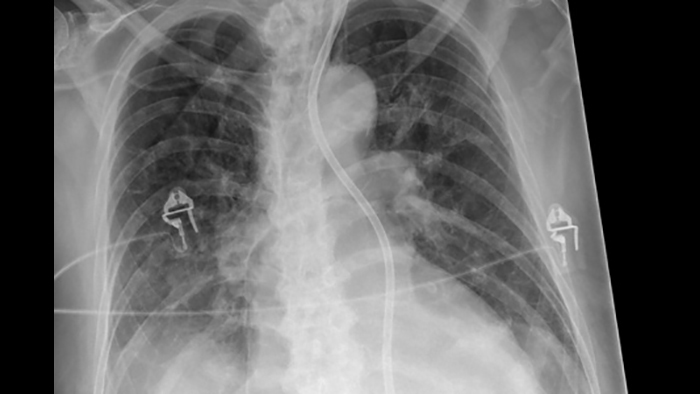

SkyFlow Plus image processing

When doing DR exams without a grid, Philips SkyFlow Plus produces images with grid-like contrast. It reduces the effect of scattered radiation for non-grid bedside chest exams. SkyFlow Plus is the industry’s first scatter correction algorithm for portable X-rays. It delivers contrast enhancement based on the amount of scatter for the individual patient.